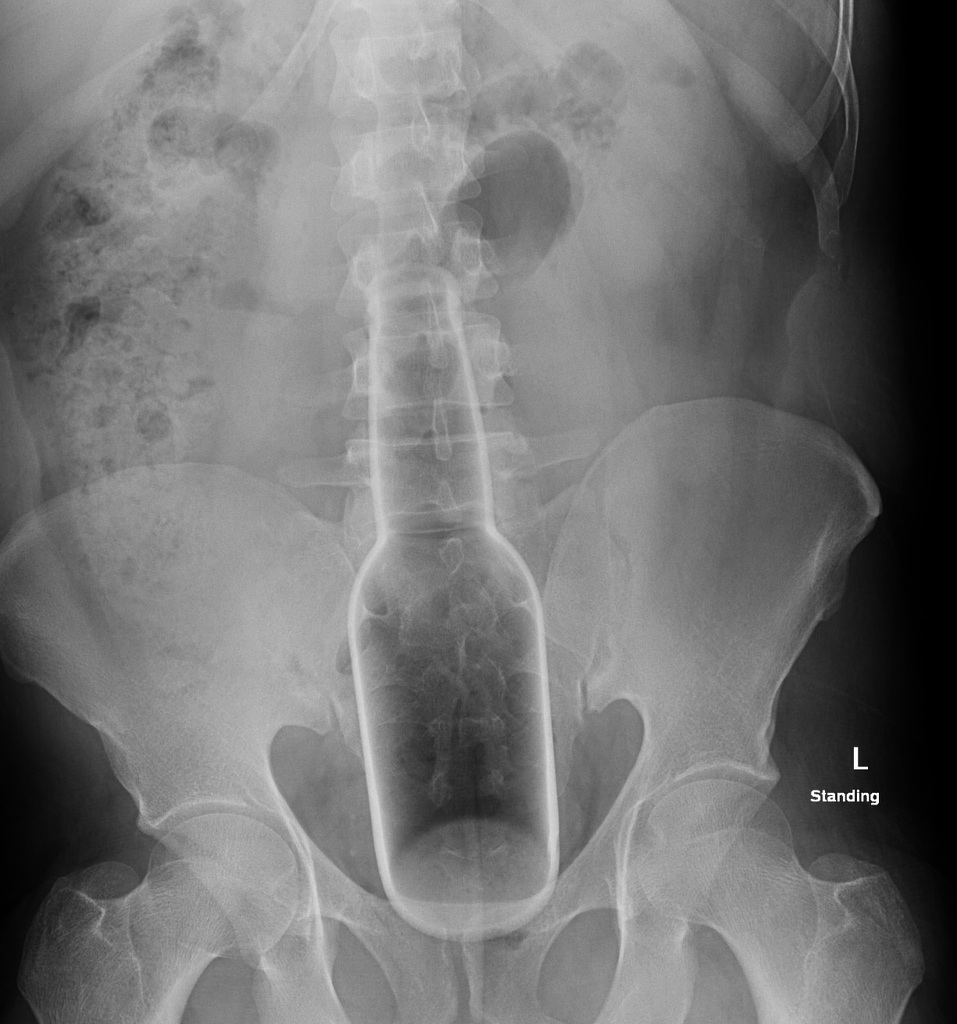

Ride em cowboy!